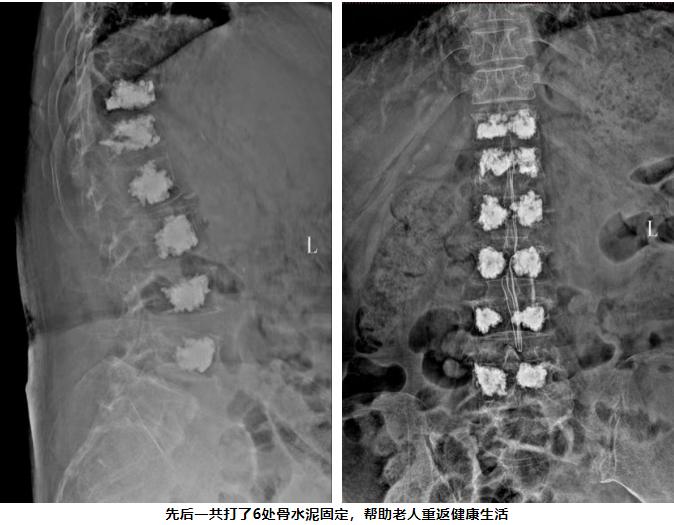

面对高龄、多病、多节段骨折的复杂情况,是选择保守治疗忍受长期卧床的痛苦,还是再次手术?我院骨科团队再次迎难而上。经过全面评估,决定为方奶奶实施“腰椎椎体后凸成形术”,一次性解决多个椎体的问题,手术非常成功!

方奶奶醒来后,紧锁的眉头舒展开了,久违的轻松感回到了她的脸上。和上次一样,术后疼痛即刻缓解,第二天,她便可以下床行走了。看着她在走廊里慢慢踱步的身影,家人悬着的心终于放下了。复查DR显示,注入的骨水泥稳稳地支撑着椎体,很快,方奶奶就顺利出院啦!